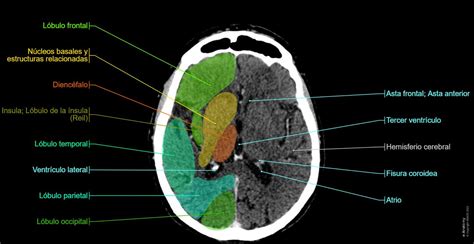

Anatomía Facial

El esqueleto facial está compuesto por 5 huesos impares: frontal, etmoides, vómer, esfenoides y mandíbula, y 6 huesos pares: cigomático, maxilar superior, nasal, cornete inferior, lacrimal y palatino. La región facial puede dividirse en 3 tercios. El superior corresponde al hueso frontal, el inferior a la mandíbula y, entre ellos, el tercio medio que se extiende desde el reborde orbitario superior hasta el proceso alveolar del maxilar superior.